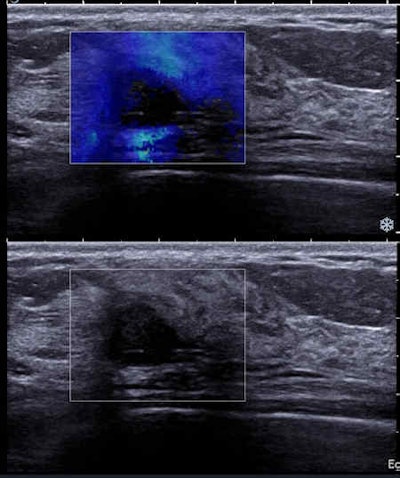

TN cancers more often had an oval shape and abrupt interface at ultrasound and rim enhancement on MRI. MRI features were suspicious for all cancers and rim enhancement of a mass was a significant predictor of triple-negative tumors (p = 0.01).

As previously noted, mammography was not the only modality used. On ultrasound, the precise description of margins improved the characterization of a mass, and in this study the two masses assigned BI-RADS ACR 3 at mammography (both TN) were classified BI-RADS ACR 4 at ultrasound because of their microlobulated or indistinct margins.

Regarding the correlation between ultrasound features and the different molecular classes, the most suspicious masses were more frequently seen in luminal tumors and oval masses with microlobulated margins, abrupt interface, and posterior enhancement in TN cancers, similar to the few correlations in the literature between ultrasound features and molecular phenotypes in all age groups.